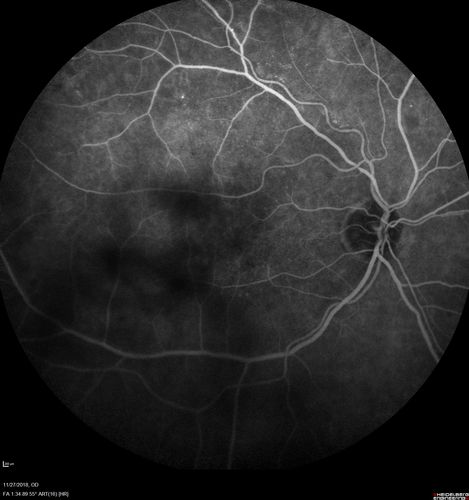

Unusual Intraretinal Deposits

71 year old diabetic man on dialysis with 20/20 vision and intraretinal deposits. Recent 150 lb weight loss, on dialysis, see album properties for full history